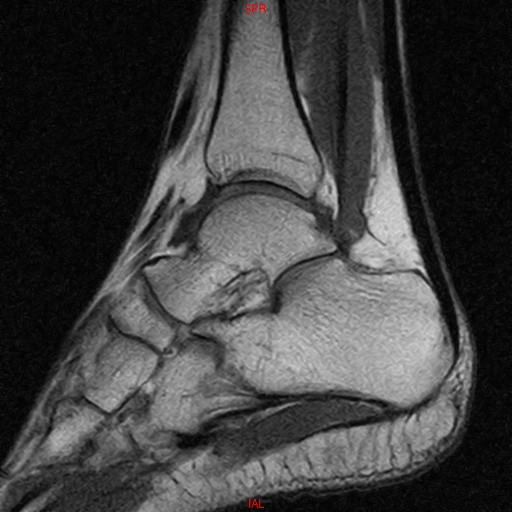

• RESONANCIA NORMAL TOBILLO SAGITAL T1